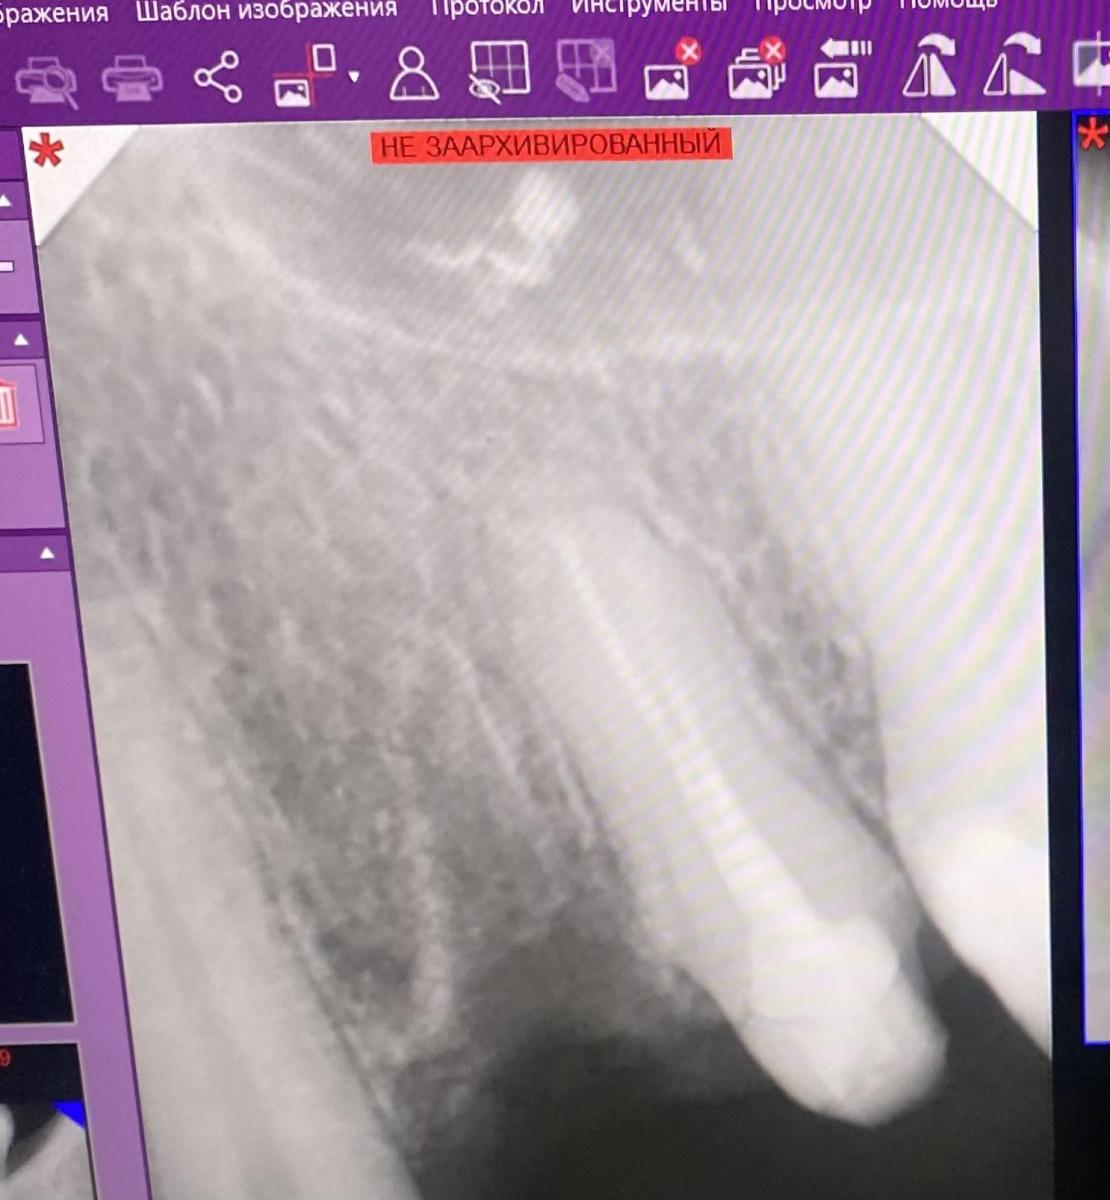

Юрий Жигурт, Добрый день! Можете ли помочь. Зуб 2.4. был с хроническим периодонтитом, воспалением, но небольшим (гранулема), восстановлен был культевой циркониевой вкладкой (без эндодонтического лечения), на тот момент зуб вообще не беспокоил, но к коронке были замечания и она была на временном цементе.

Прошло 3 месяца, стала появляться болезненность. Со слов врача, каналы были непроходимыми, поэтому он не стал их пролечивать при восстановлении вкладкой (я не знала тогда даже о гранулеме, врач также ничего не сообщил о непроходимости каналов зуба).

29.09.2025 стала болеть область над зубом под губой (область корня 2.4 и даже к 2.3 распространяться)., хирург предположил, что это как раз воспаление то обострилось, из 2 вариантов: резекция верхушки или удаление зуба больше аргументов было в пользу последнего, так как иначе вкладка осталась бы «висеть», гарантий никто не дал бы.

02.10.2025 врач удалил зуб 2.4, уже прошло 3 недели, но у меня все еще сильное воспаление. Лунка зарастает, но очень медленно, сегодня – 22.10.2025 появилась опять отечность, ощущение горечи, как было первые дни, левый глаз словно «тянет» все эти дни и главное, что болезненность на десне у корня зуба 2.4, из-за которой было принято решение об удалении зуба, ТАК И ОСТАЛАСЬ. Зуб уже не вернуть, но с этой болью невозможно быть. Хирург будет только 30.10.2025 г., другие специалисты клиники (ортопед, терапевт) не видят в заживлении ничего страшного и даже снимок не делают. Но боль не уменьшается, также болит голова(левый висок), тянет много дней "левый глаз" и болезненность именно под губой наверху, прямо на стыке губы и кости.

Сегодня сделала снимок в другой клинике, но здесь не прикрепить. Можете ли помочь, с чем связана тянущая боль и отечность слизистой? Неужели это инфекция или гайморит, может была перфорация какая-то. Нос дышит, температура не поднимается в последнюю неделю, но вся левая щека словно горячая, наверху на левой стороне все болит. Может, застудила или что-то нервное.

yuliya--guseva, почему "здесь не прикрепить"?

Юрий Жигурт, извините, не сразу получилось прикрепить, только после авторизации. Я просила сделать фото именно этой зоны, где болит.

yuliya--guseva, ещё фото десны сделайте, пожалуйста!?

Юрий Жигурт,

Юрий Жигурт, сегодня ночью не спала. Боюсь, что это альвеолит, перешедший в периостит.

yuliya--guseva, спасибо!

Предполагаю, что что-то осталось!?

Я бы сделал дополнительную чистку...

Юрий Жигурт, большое спасибо за ответ! 23.10.2025 рентген делала еще в другой клинике, сказали, что осколков нет. Можете, пожалуйста, тоже посмотреть?

И если будут чистить лунку и все же найдут часть зуба, то надкостница потом заживет, да?

yuliya--guseva, это зачем? Надо исключить пульпит клыка...